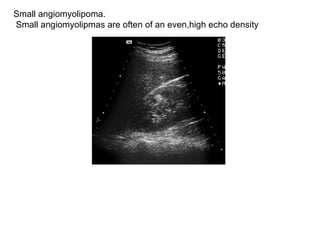

Small angiomyolipoma. Small angiomyolipmas are often of an even,high echo density